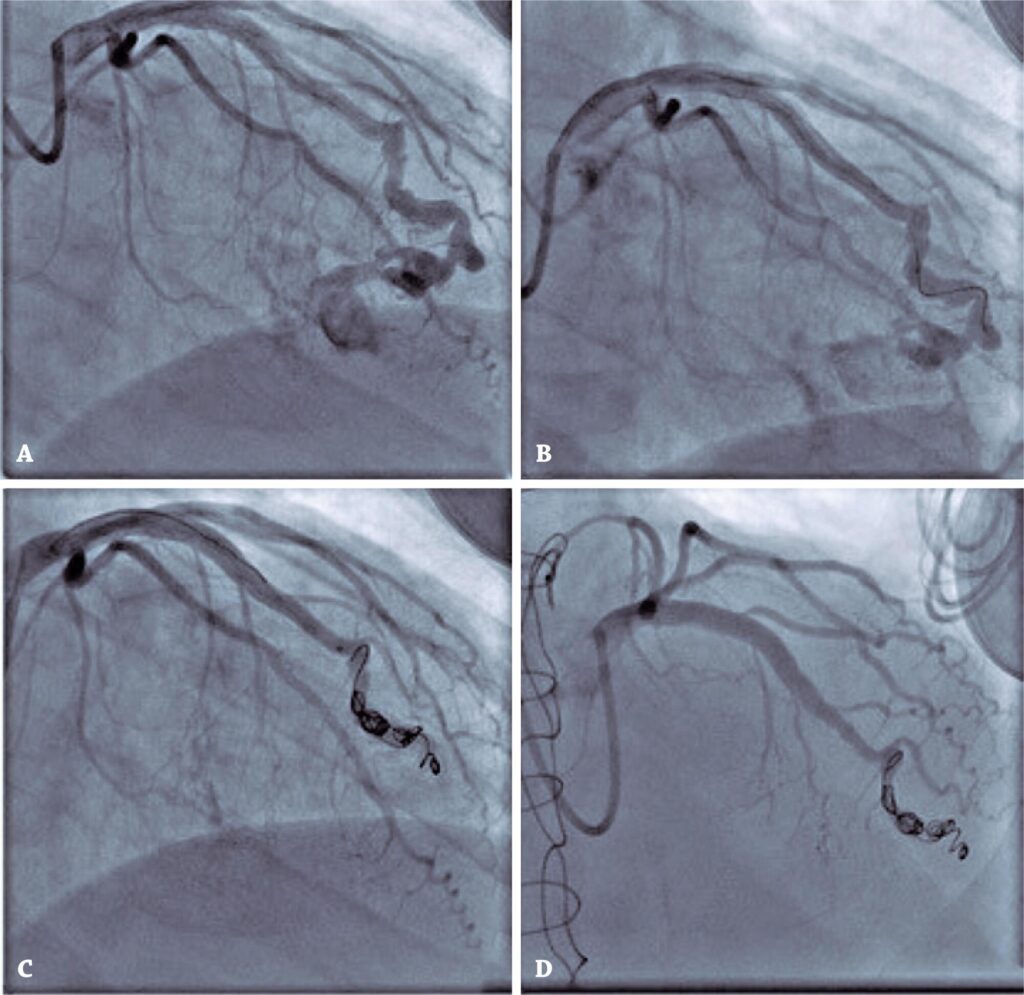

After the scintigraphy finding of ischemia, a coronary angiography was performed, which displayed a fistula between the left anterior descending artery and right ventricle with subsequent coronary occlusion (). This is a rare complication of endomyocardial biopsy.

Figure 1

(A) Fistula between the left anterior descending artery and right ventricle with subsequent coronary occlusion. (B and C) Coils deliverance. (D) Final angiography.